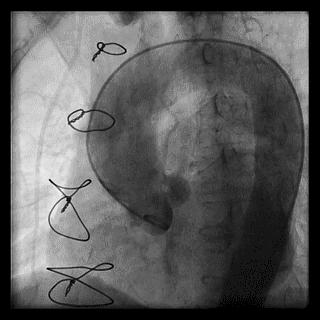

(4)LIMA桥血管造影

首选导管:JR4.0导管

其他导管:如果开口明显成角应选用专用的内乳动脉造影导管

➢ CASE 6

经股动脉途径TIG,非选择造影如果能清晰显影,可不做超选造影

➢ CASE 7

经左侧桡动脉途径JR4.0,非选择造影如果能清晰显影,可不做超选造影